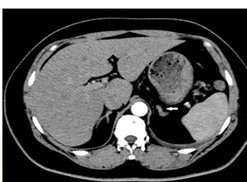

肾上腺CT正常表现

1.形态:形态各异;右侧:斜线状、倒“V”、倒“Y”形;左侧: 倒“V”、倒“Y”形或三角形;三维重建呈叶状。

2.大小: 侧支厚度<10mm;侧支厚小于同侧膈肌脚,面积小于150mm。

3.密度: 均匀,边缘光滑,无外凸结节。

4.强化: 均匀,边缘光滑。

肾上腺腺瘤CT表现

1.肾上腺腺瘤发生于肾上腺皮质,含脂质;

2.直径多小于3cm;

3.CT值<10HU;

4.出血、坏死、囊变少见;5.CT增强:早期快速廓清